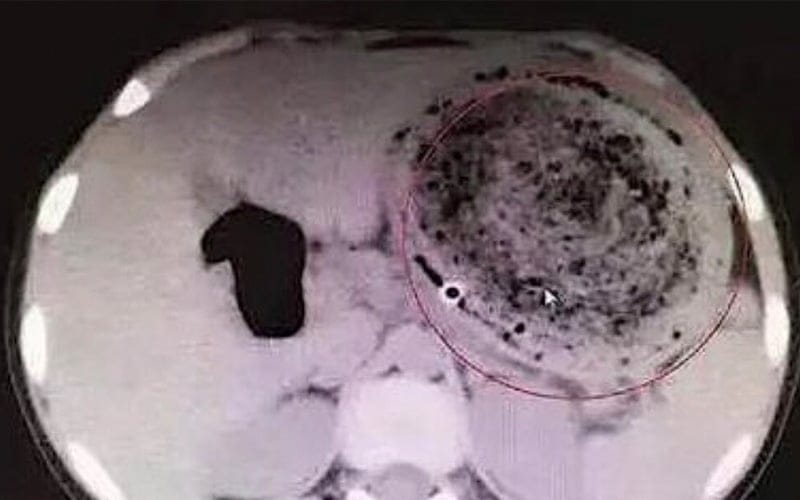

Pemeriksaan imbasan tomografi berkomputer oleh sekumpulan doktor di hospital itu membawa kepada penemuan objek asing itu.

Akhirnya sekumpulan doktor di hospital Donghua, Guangdong, China berjaya mengeluarkan gumpalan rambut seberat 1.5 kilogram (kg) dari dalam perut kanak-kanak itu.